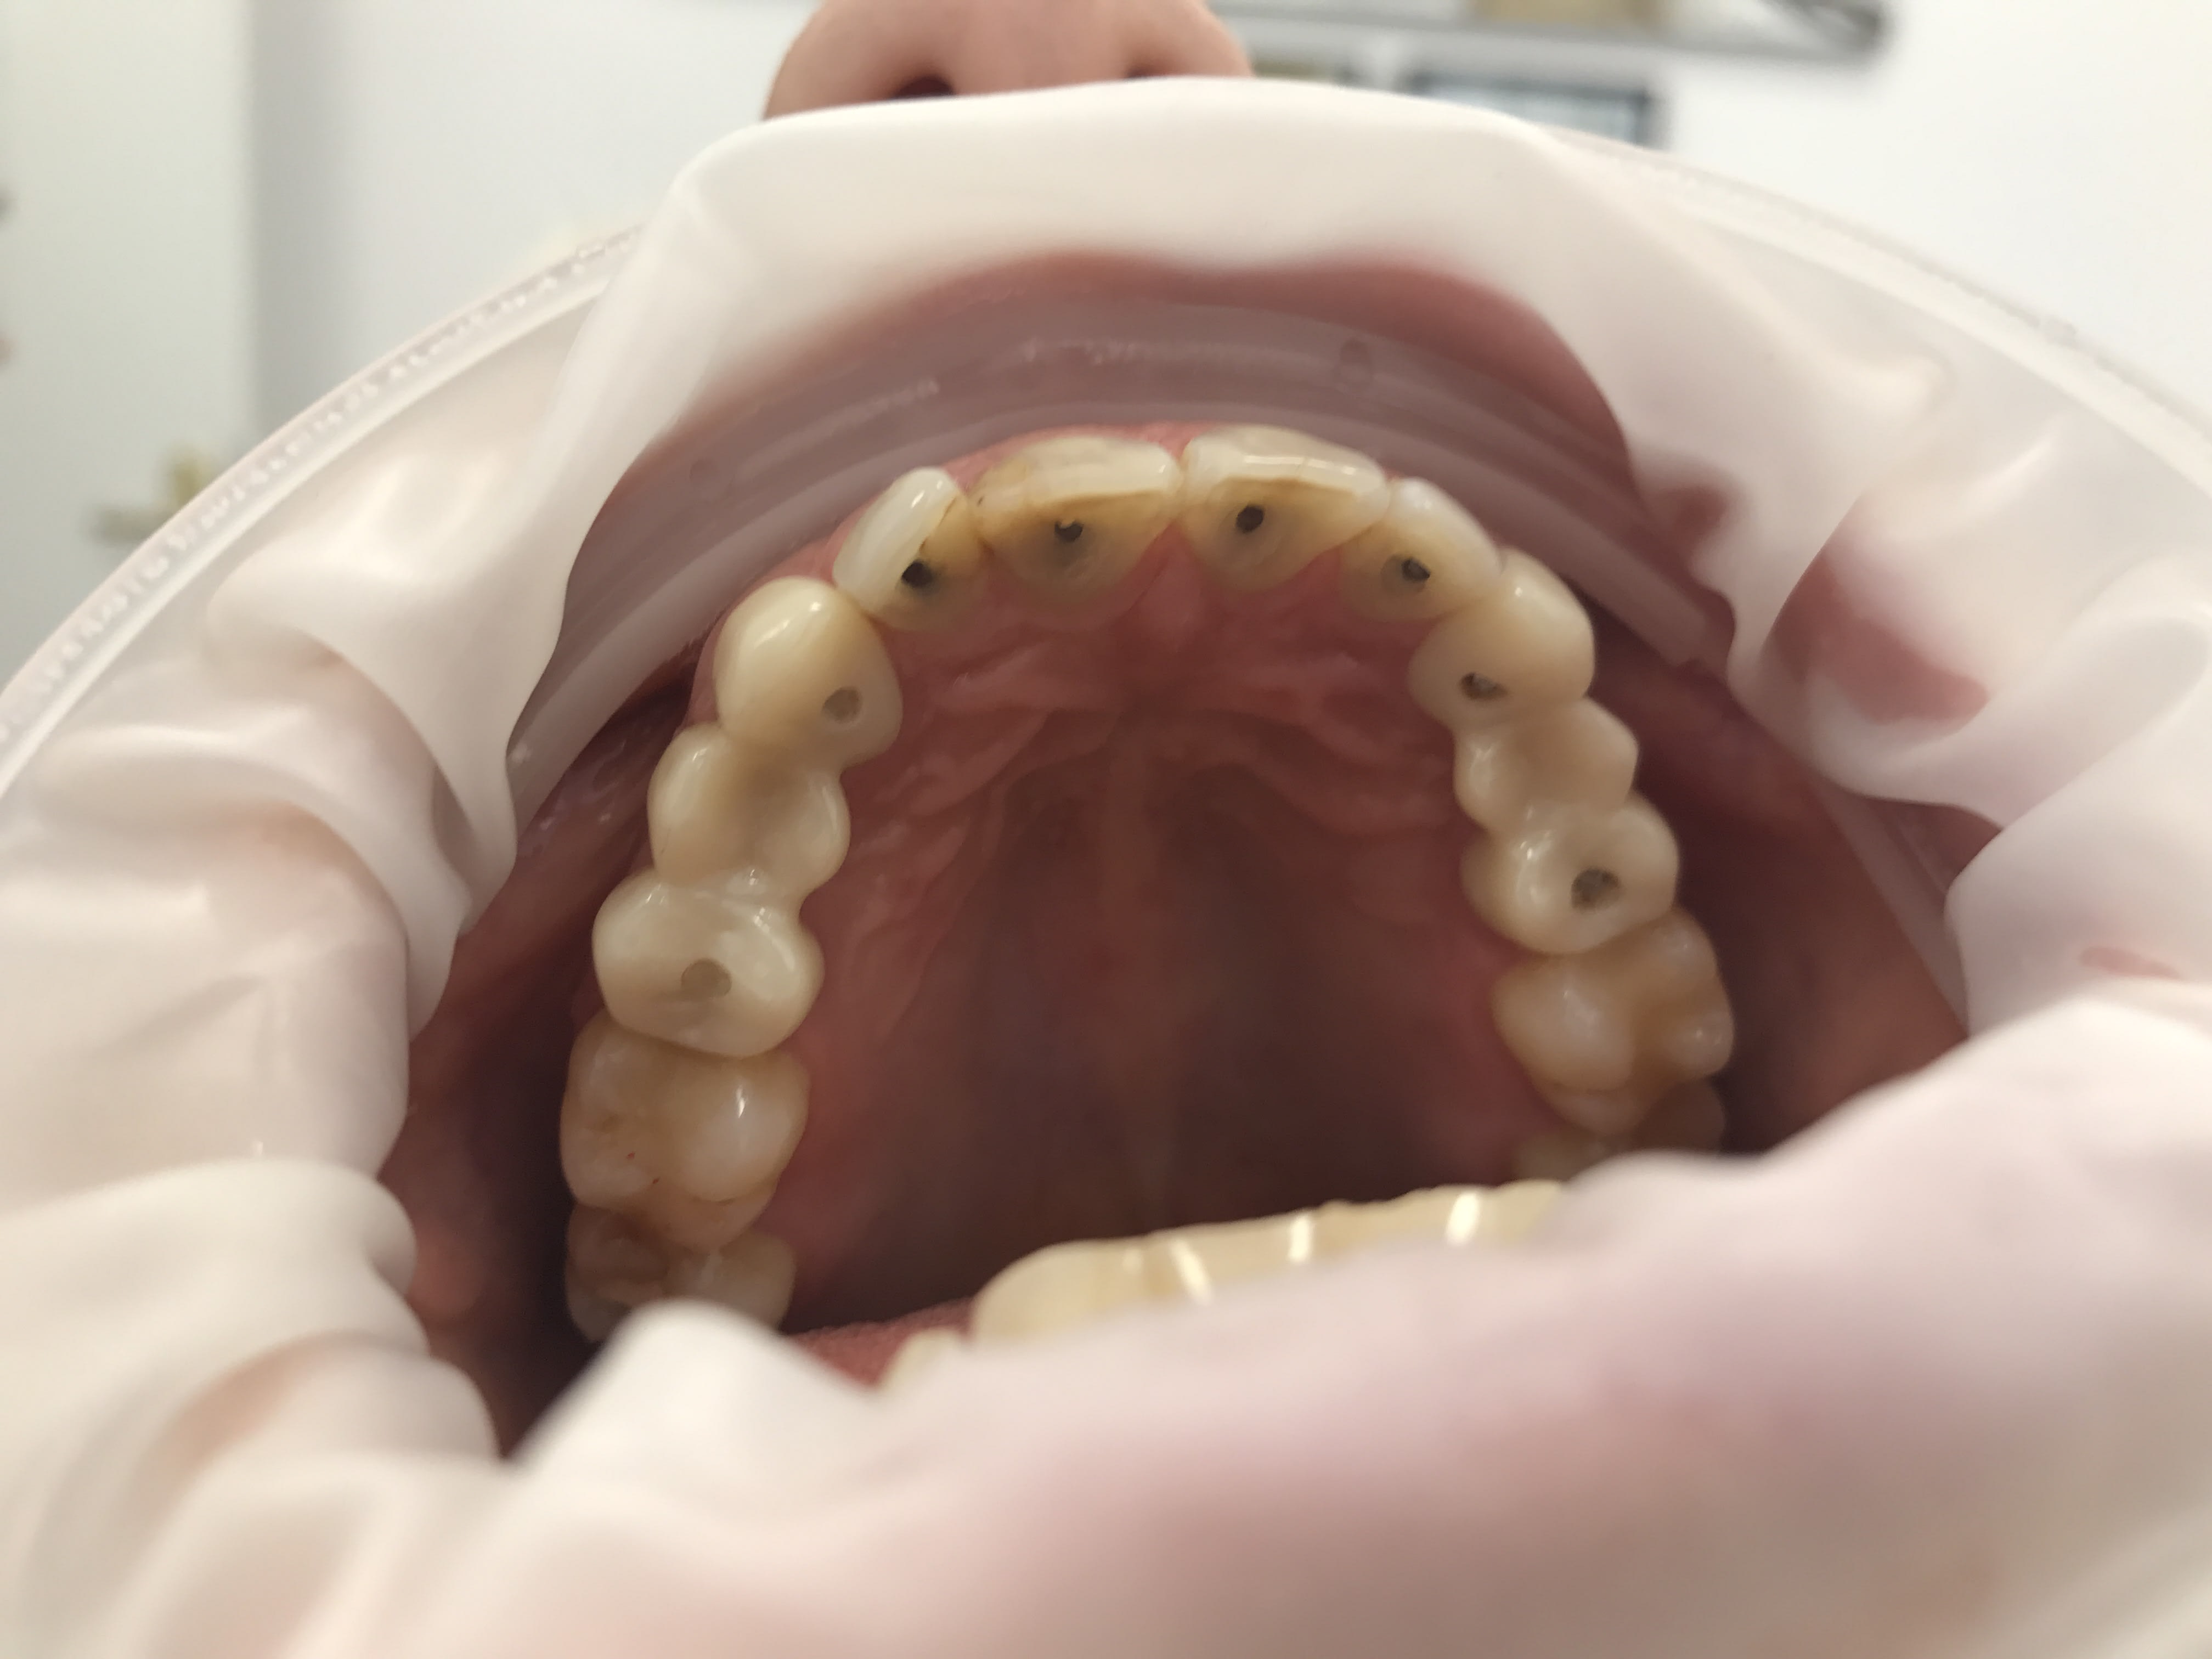

Bon et bien voila ou on en est aujourd'hui

Img 1461 odo6eo - Eugenol

Img 1452 fsszmf - Eugenol

Img 1443 yrolq8 - Eugenol

Img 1457 r2aopb - Eugenol

Img 1448 ekmmyu - Eugenol

iyaudat

31/07/2017 à 19h43

Les photos ne sont pas dans l'ordre je sais pas pourquoi.

Et bien voilà le patient en a pour son argent ... enfin la sécu.

Well done !

Y a plus qu'à tout passer au taille crayon ... ;) (j'imagine que tu n'as pas facturé de RTE?)

Effectivement pas facturé les rte...